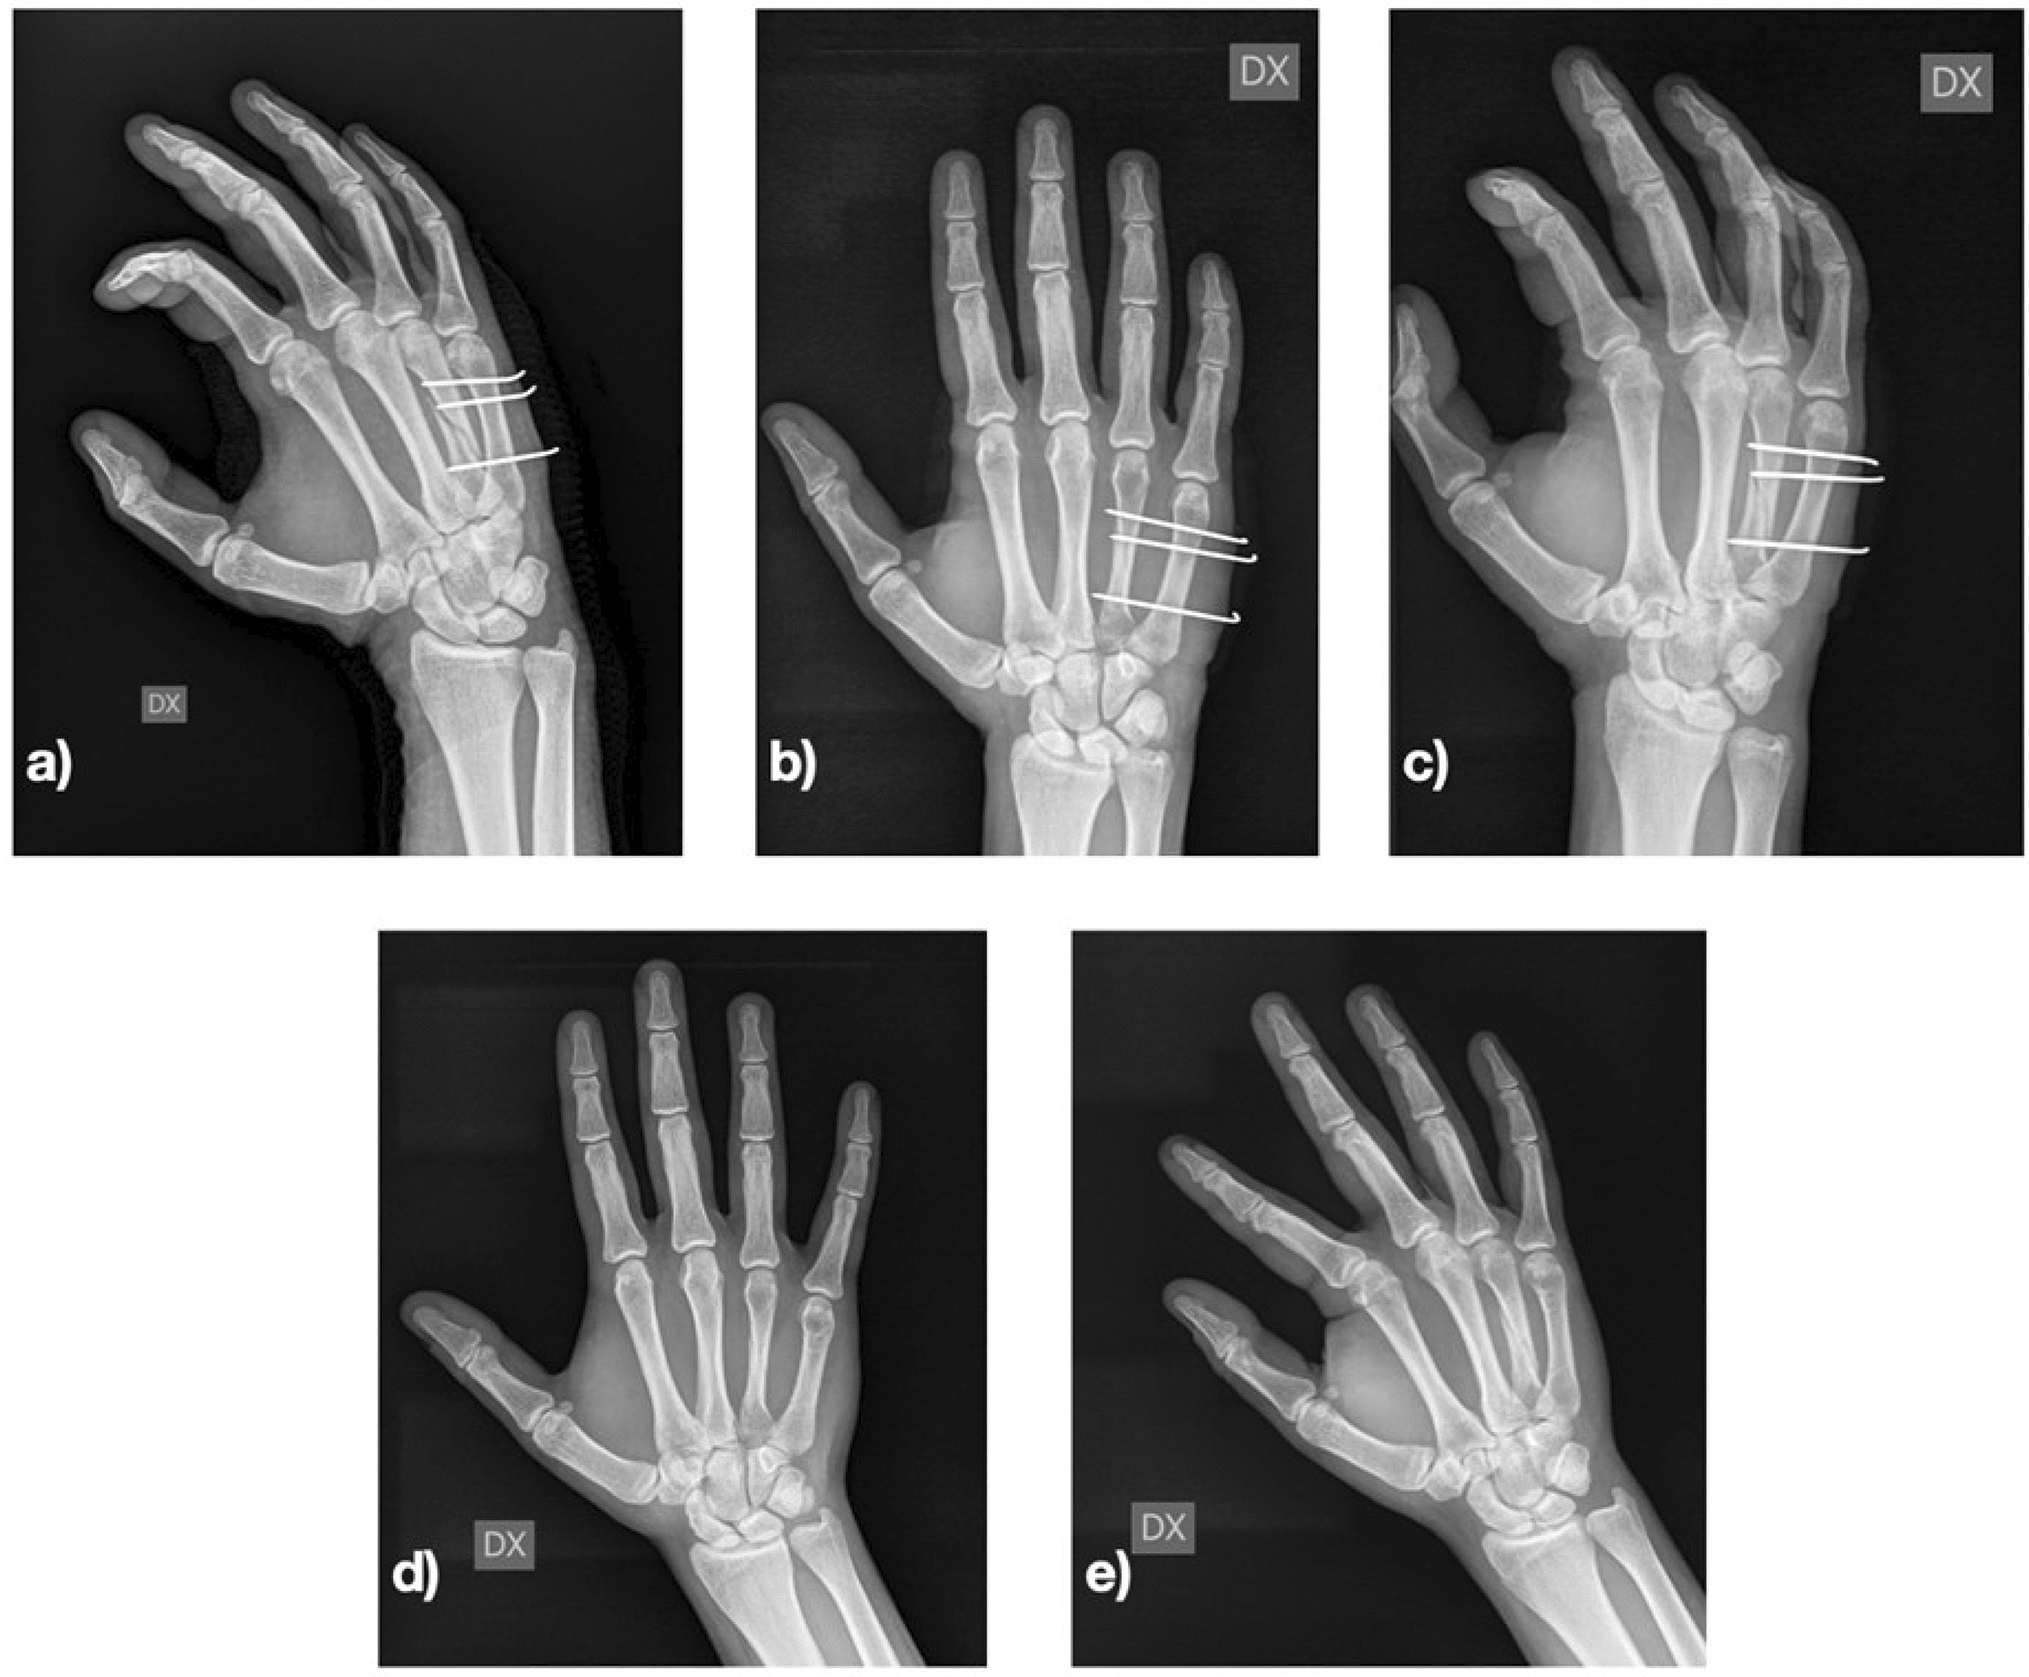

All patients underwent loco-regional anaesthesia. As antibiotic prophylaxis, 2 g of intravenous cefazolin were administered before surgery. Closed reduction of the fracture was performed under image intensification. In some fractures, especially spiral or severely displaced (11 of 56), open reduction was necessary, performing a dorsal mini-incision to reduce the fracture as anatomically as possible. The most important target was to correct the rotational deformity. Fixation was performed with 1 or 2 K-wires 1.2 mm in diameter proximal to the fracture and with 1 or 2 K-wires distal the fracture to avoid displacement in the sagittal plane of the distal portion of bone. The K-wires were advanced through the fractured metacarpal up to the far cortex of the adjacent metacarpal (Figs. 1 and 2).

Fig. 1

Fourth metacarpal spiral fracture. a post-operative radiography; b and c 1-month post-operative radiography; d and e 3-month post-operative radiography